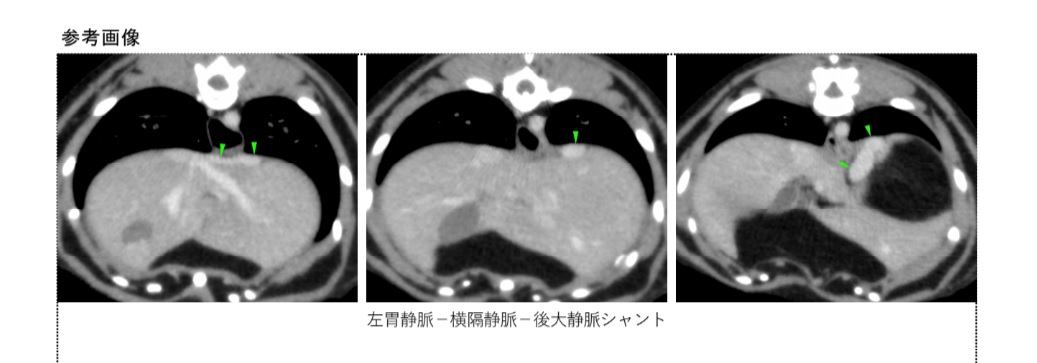

血液検査で高アンモニア血症、貧血、尿素窒素やクレアチニン値の低下が発見されます。超音波検査は非侵襲的で麻酔の必要もなく簡便な検査と言えます。造影CT検査では、シャント血管を完全に描出でき、手術を計画する上でも非常に有用な検査となります。

造影されたシャント血管